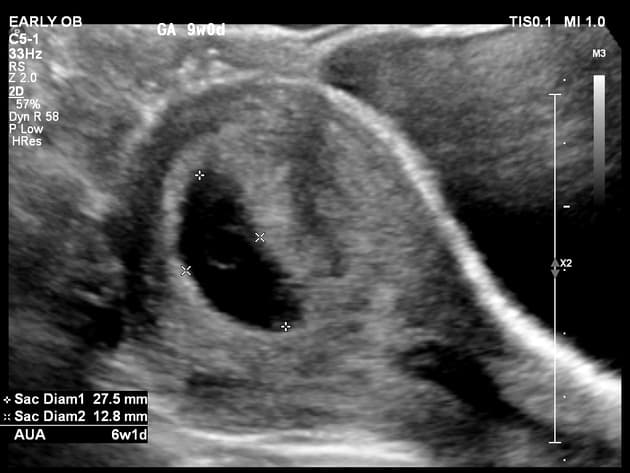

tuổi thai ≤6,2 tuần (chiều dài đầu mông ≤4 mm)

tuổi thai 6,3–7,0 tuần (chiều dài đầu mông 5–9 mm)